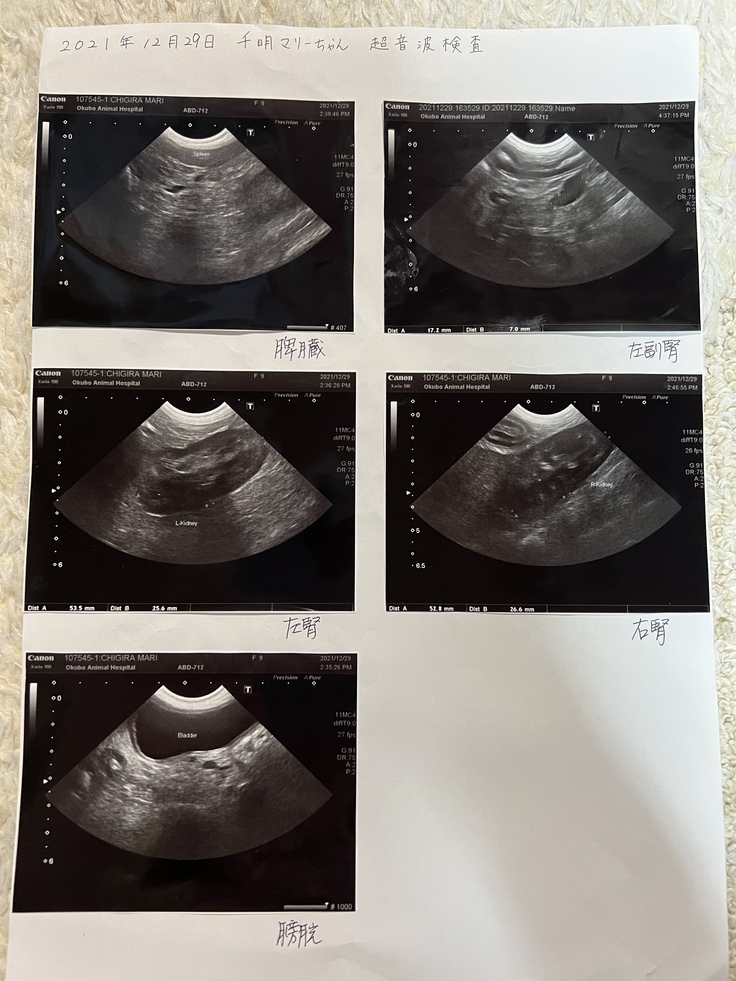

何ヶ月も通院し、超音波検査もしました。その時、腸の幅がおかしいと言われました。心配で、後日また診てもらいましたが、胆嚢に胆石があり、年内に摘出した方が良いと言われました。腸の事は後回しにされたのです。

超音波検査も含め、詳しく調べてもらう事に。

白血球が異常に多く、低アルブミン血漿、貧血、超音波検査では腸管には粘膜肥厚が見られました。胆嚢粘液嚢腫?胆嚢の中に胆石もあるけど、ゼリーとかキウイみたいのがあるらしいです。まだ余力はあるがやはり手術はしないといけないそうです。

超音波検査や血液検査、全てやってもらう事に。